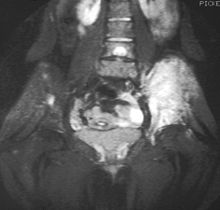

MRI will show the full bony and soft tissue extent and relate the tumor to other nearby anatomic structures (e.g. vessels). Gadolinium contrast is not necessary as it does not give additional information over noncontrast studies, though some current researchers argue that dynamic, contrast-enhanced MRI may help determine the amount of necrosis within the tumor, thus help in determining response to treatment prior to surgery. Computed axial tomography (CT) can also be used to define the extraosseous extent of the tumor, especially in the skull, spine, ribs, and pelvis. Both CT and MRI can be used to follow response to radiation and/or chemotherapy. Bone scintigraphy can also be used to follow tumor response to therapy. In the group of malignant small round cell tumors that includes Ewing sarcoma, bone lymphoma, and small cell osteosarcoma, the cortex may appear almost normal radiographically, while permeative growth occurs throughout the Haversian channels. These tumors may be accompanied by a large soft-tissue mass while almost no bone destruction is visible. The radiographs frequently do not shown any signs of cortical destruction. Radiographically, Ewing's sarcoma presents as "moth-eaten" destructive radiolucencies of the medulla and erosion of the cortex with expansion.[citation needed]

MRI slice showing Ewing sarcoma of the left hip (white area shown right)